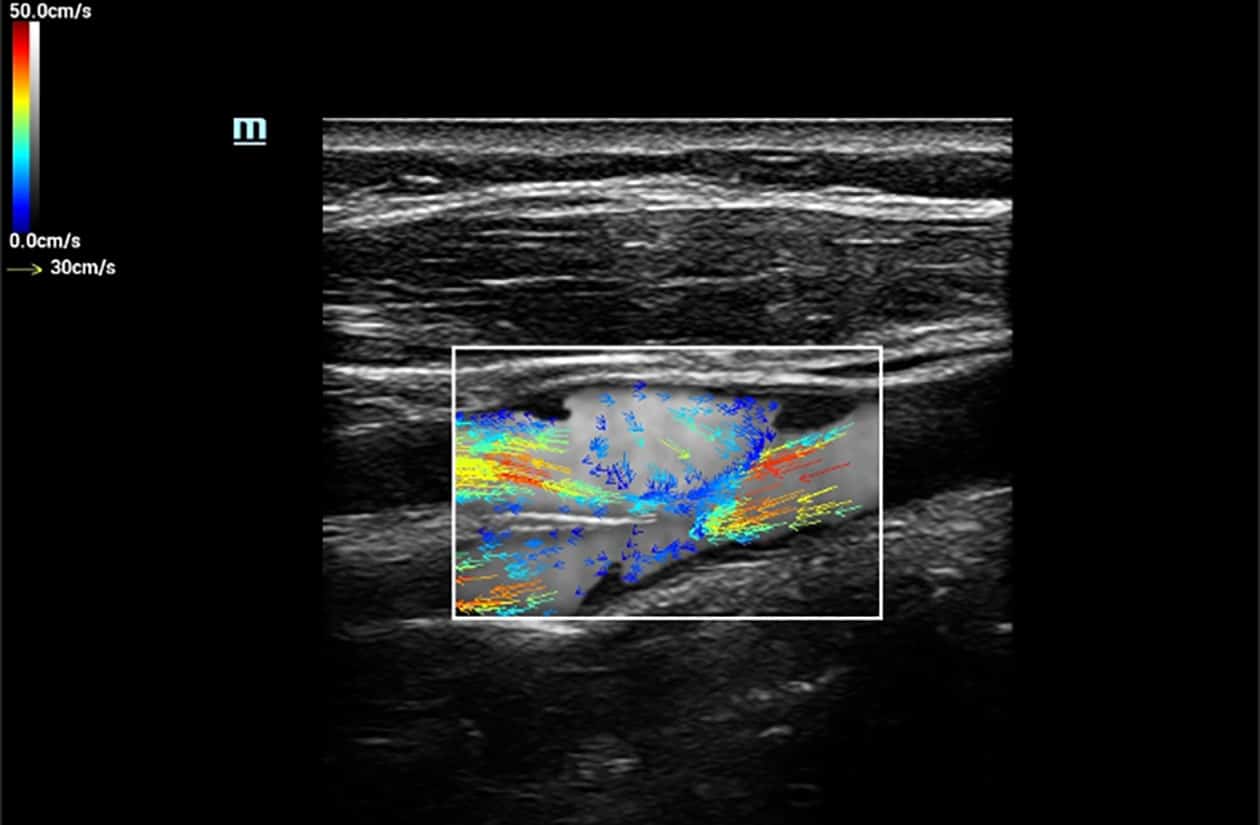

V Flow

V Flow imaging creates a quantitative map of hemodynamic states by tracking the acoustic speckle produced by microstreams of red blood cells as they flow through several non-temporally coherent transmit plane waves. The resulting information is plotted as arrows of varying lengths and colors expressing direction and velocity of blood within the interrogated area.